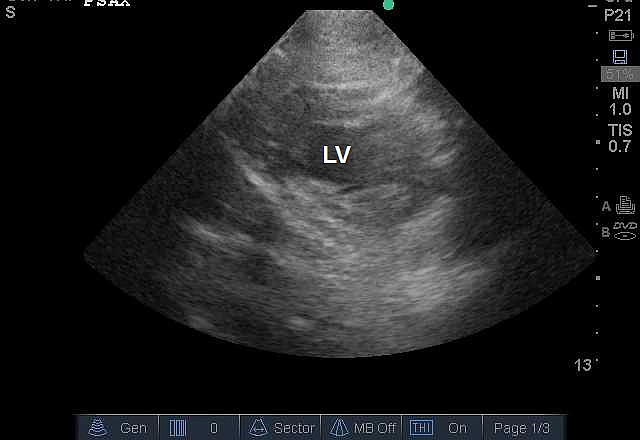

Case 7-2. Parasternal Short-axis View at the Midventricular Level

Video 7-2A. Left ventricular (LV) function is normal. The right ventricle is normal in size and there is no septal dyskinesia.

Video 7-2B. Normal LV function but with increased LV wall thickness. There is also a circumferential pericardial effusion. Strictly speaking, ventricular hypertrophy requires a formal measurement of ventricular muscle mass that requires a series of specific measurements that are not within the purview of basic critical care echocardiography. The intensivist should report increased wall thickness consistent with ventricular hypertrophy, and consider alternative causes for increased wall thickness. In this case, the patient had advanced amyloidosis.

Video 7-2C Severe LV dysfunction with segmental wall abnormality. The anterior mid septum is akinetic while the inferior and lateral walls are contracting although to reduced extent. The anterior and anterolateral walls are not well visualized due to a rib shadow. Adequate image quality in all views is frequently not possible in the critically ill. The subcostal short-axis view would be an alternative.

Video 7-2D. Severe LV dysfunction with a segmental wall pattern. The septal function is very reduced as is the anterior wall, suggesting a left anterior wall infarction, while the inferior, infero lateral, and anterolateral segments are reduced in function but to lesser extent. There is a pleural effusion with atelectatic lung within it. At the end of the clip, the tomographic plane changes to the mitral level. This resulted from respiratory translation movement of the heart, which is a common artifact of echocardiography performed in the patient with respiratory distress.